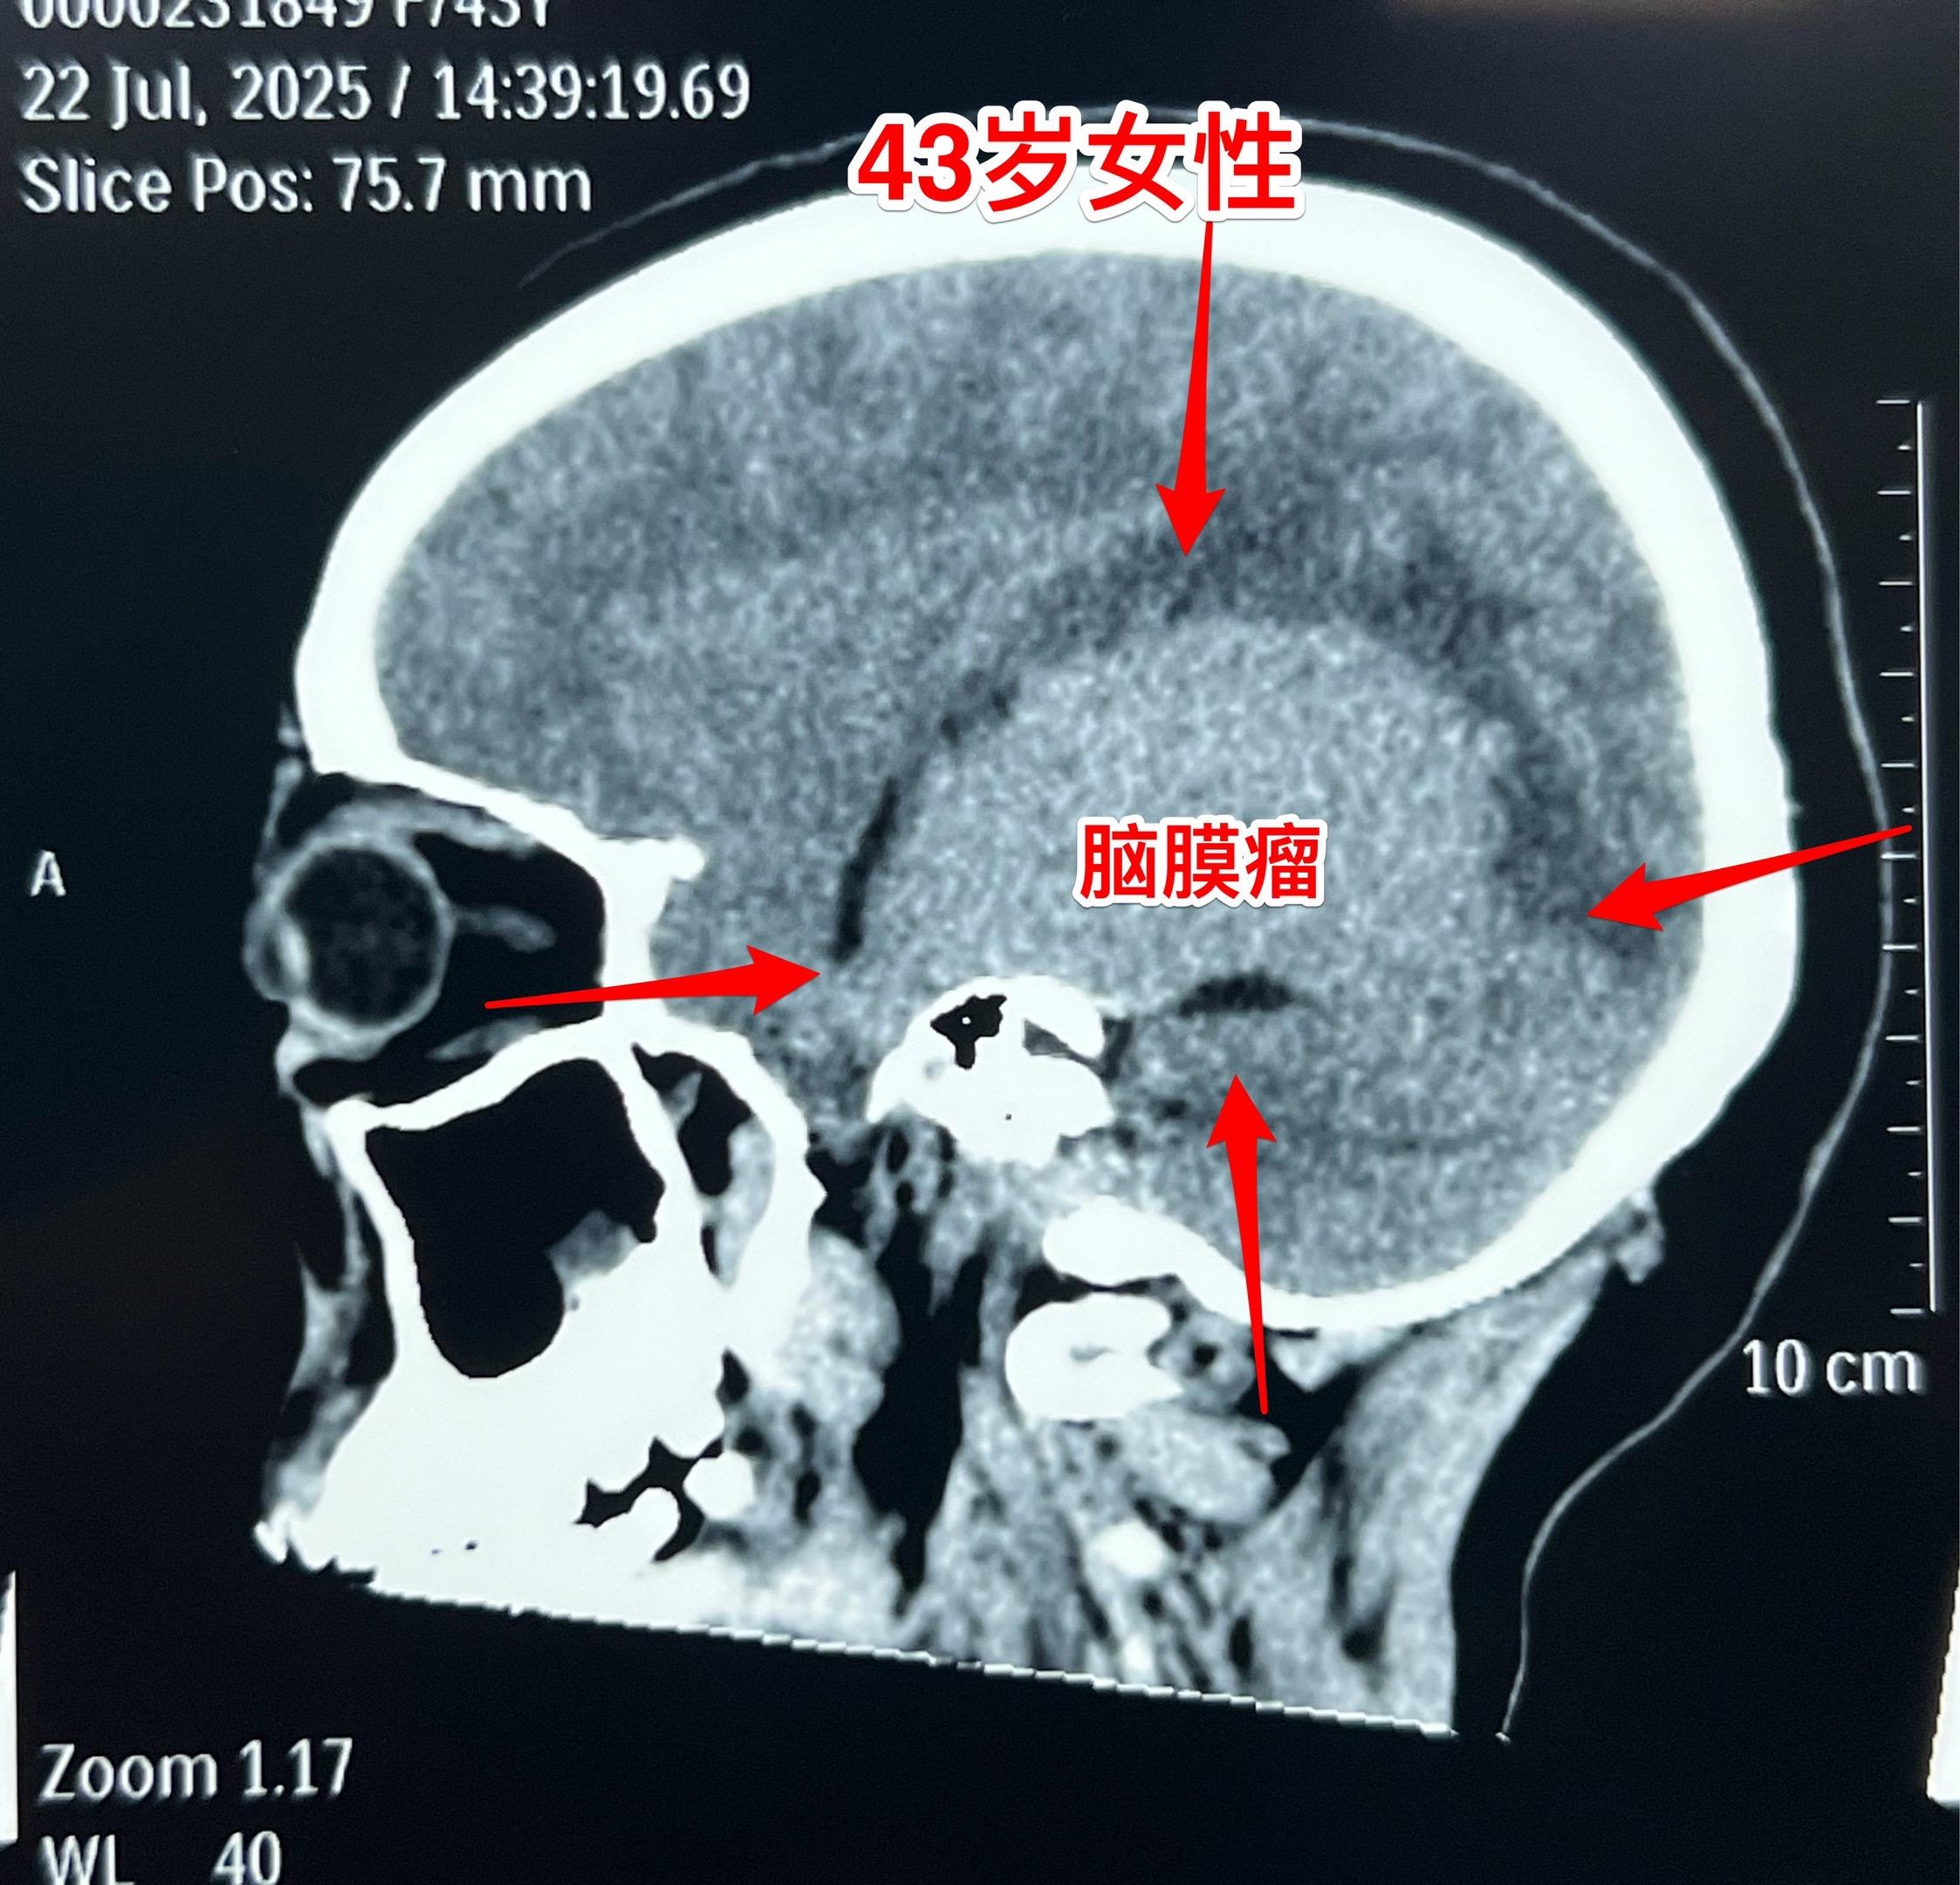

藏族牧民脑肿瘤被发现时像鸡蛋一样大。青海省黄南州藏族牧民,43岁,女性,平时以放养牦牛为生,家里有一百多头牦牛,她夫妻二人完全不能说汉语。 她头痛五年了,视力下降一年,迟迟没有就医,今年七月份因视力很差了才到西医医院检查,发现病根儿是脑膜瘤。如图所示,脑膜瘤像鸡蛋一样大。 发现脑肿瘤后,他们第一步是找活佛预判凶吉,指导治疗方向! 2025年8月1日作了手术,将肿瘤完全切除。希望她能顺利出院!